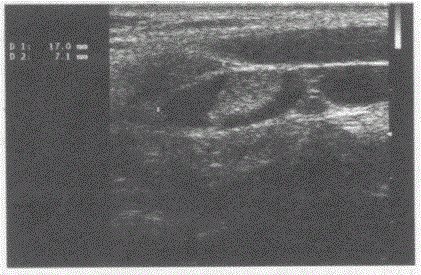

问题 临床资料:男,25岁,自述发热,嗓子痛。 临床物理检查:扁桃体红、肿大,体温39.0℃。 超声综合描述:双侧颈部血管旁可见数个两头稍尖长圆形低回声,最大1.7cm×0.7cm,边界清晰,长径/短径比值(L/S)≥2。 超声提示:

选项 A.颈淋巴瘤 B.双侧颈部肿大淋巴结(颈淋巴结炎) C.颈淋巴结结核 D.颈部正常淋巴结

答案 B